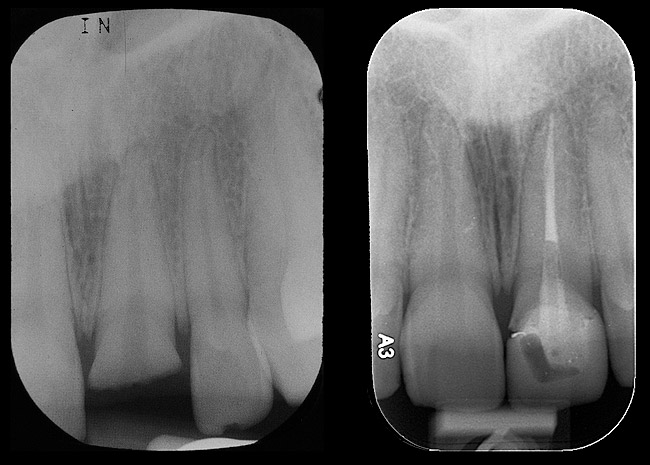

Figure 10  Tooth No. 9, pretreatment, showing Ellis Class III crown fracture; completed endodontic treatment, provisional post and core—periapical views.

Figure 10

Emergency endodontic treatment had been completed to manage the traumatically exposed root canal; Figure 10 shows the pre-treatment (Ellis Class III crown fracture) and post–endodontic-treatment periapical views of tooth No. 9. The restorative dentist temporarily cemented a glass-reinforced fiber post and used a fiber-reinforced composite core buildup material as an immediate provisional. Several weeks later, a provisional bis-acryl temporary crown on No. 9 was cemented on a larger-diameter glass-reinforced fiber post retaining a new fiber-reinforced composite core. Figure 11 shows the final feldspathic porcelain crown placed by the restorative dentist. During the fabrication and cementation of this crown, the remaining root appeared intact and the tooth was asymptomatic.

Radiographic evidence of external root resorption on tooth No. 26 and periapical radiolucencies with a history of prior endodontic treatment, including apicoectomies, were present on the mandibular central incisors (Figure 2).

Figure 2  Initial periapical radiographs showing failed endodontic treatment of Nos. 24 and 25, and root resorption, No. 26.

Figure 2